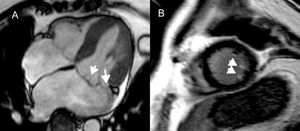

La valvulopatía mitral degenerativa puede afectar al engrosamiento de las valvas, la redundancia, la elongación de las cuerdas, la dilatación anular y la dinámica anular anómala95,96. Las fuerzas mecánicas ejercidas por las valvas y las cuerdas posiblemente afecten repetidamente al músculo papilar y el miocardio subyacente, lo que a la larga cuasa la formación de cicatrices en el miocardio95. El RTG en el músculo papilar y la pared inferobasal del VI se correlaciona con la aparición de AV95. Se constata RTG en el músculo papilar (en especial en los extremos, junto a la inserción de las cuerdas) en el 63% de los pacientes con prolapso de la válvula mitral y se relaciona con AV (figura 6)4,97.

Realce tardío de gadolinio en la resonancia magnética cardiaca de pacientes con prolapso de la válvula mitral. A: imagen de precesión libre en estado estacionario horizontal de eje largo, que muestra el prolapso de ambas valvas de la válvula mitral. B: proyección de eje corto, con realce tardío de gadolinio de los extremos del músculo papilar, que se ha vinculado a arritmias ventriculares95. Reproducido con autorización de Van der Bijl et al.4.